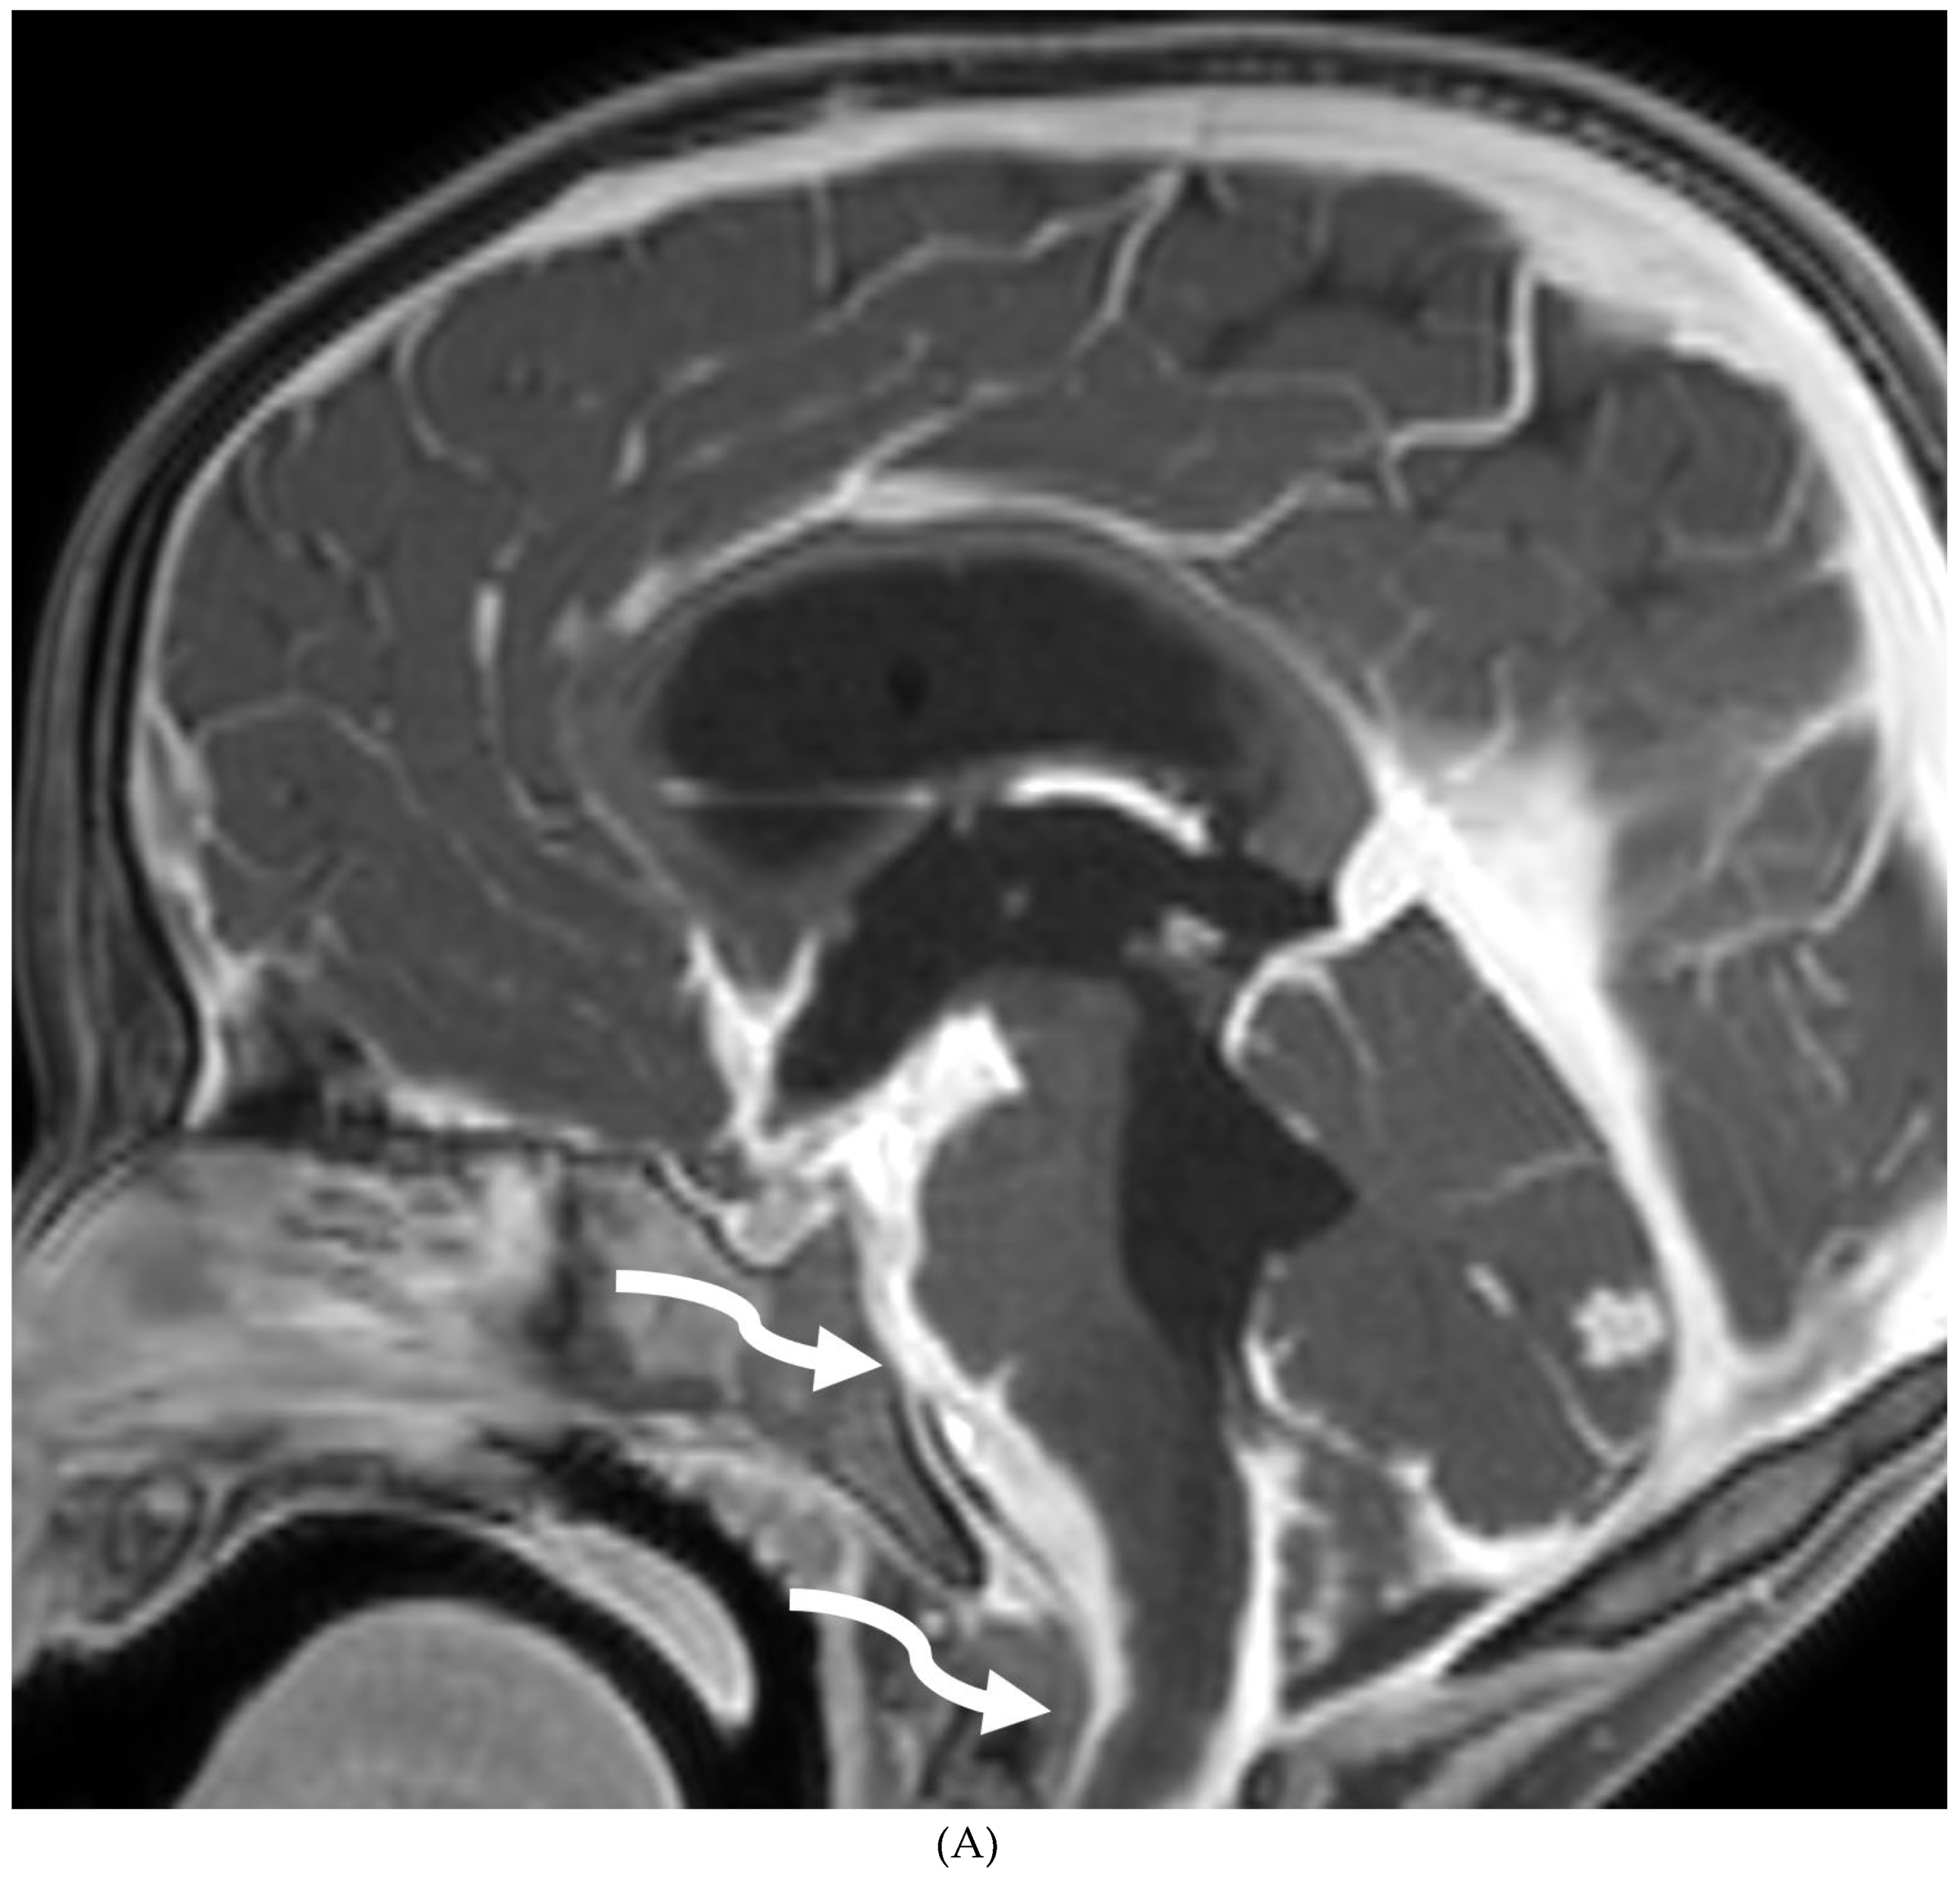

INTRACRANIAL HYPOTENSION (IH)

- Peterson EE, Riley BL, Windsor RB. Pediatric Intracranial Hypotension and Post-Dural Puncture Headache. Semin Pediatr Neurol. 2021 Dec;40:100927. Epub 2021 Sep 3. PMID: 34749914. [CrossRef]

- Schievink WI, Maya MM, Louy C, Moser FG, Sloninsky L. Spontaneous intracranial hypotension in childhood and adolescence. J Pediatr. 2013 Aug;163(2):504-10. Epub 2013 Feb 28. PMID: 23453548. [CrossRef]

- Shah LM, McLean LA, Heilbrun ME, Salzman KL. Intracranial hypotension: improved MRI detection with diagnostic intracranial angles. AJR Am J Roentgenol. 2013 Feb;200(2):400-7. PMID: 23345364. [CrossRef]

- Yuh EL, Dillon WP. Intracranial hypotension and intracranial hypertension. Neuroimaging Clin N Am. 2010 Nov;20(4):597-617. PMID: 20974378. [CrossRef]